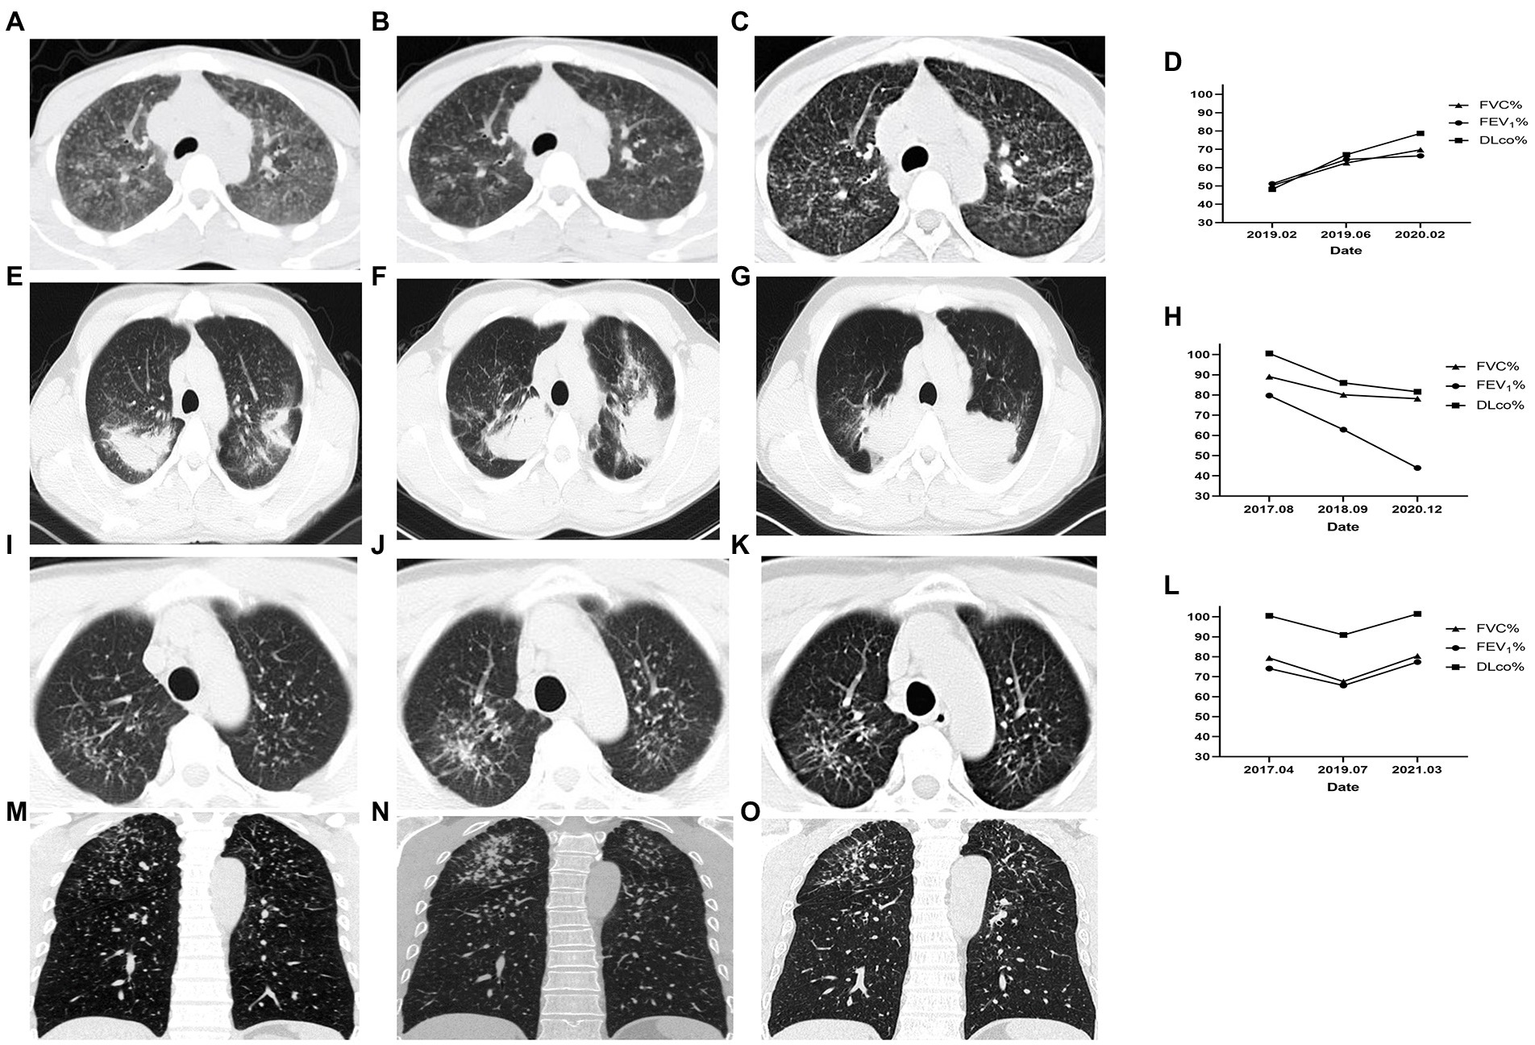

In Case 1, a 26-year-old male in observation group with 5 years of exposure, the manifestation observed in the HRCT images did not show deterioration over 31 months and pulmonary function improved. In Case 2, a 29-year-old male in the control group with 6 years of exposure, aggravated on HRCT and pulmonary function over 32 months. In Case 3, a 44-year-old male in observation group with 8 years of exposure, HRCT progressed and pulmonary function decreased in 27 months after first registration and improved after 20 months’ treatment with Tet (Figure 2).

Figure 2. Changes of HRCT and pulmonary function of representative cases. Case 1 of the observation group. (A) HRCT showed diffuse GGOs, extensive nodular opacities, and para-aortic lymph node enlargement at baseline. (B) GGOs was significantly reduced after 4 months. (C) GGOs dissipated without coalescence or PMF emerging after 31 months of treatment. (D) The pulmonary function indexes FVC%, FEV1%, and DLco% showed an increasing trend. Case 2 of the control group. (E) HRCT showed PMF on bilateral lungs at baseline. (F) The left lung PMF enlarged and the right lung PMF contracted centripetally with emphysema developing 13 months later. (G) The lesion on HRCT continued to progress and the emphysema worsened. (H) Correspondingly, the pulmonary function gradually decreased. Case 3 began Tet treatment after the second HRCT. (I,M) Cross-sectional and coronal HRCT images showed diffusely distributed nodules at baseline. (J,N) Nodule opacities increased and coalescence emerged in the right upper lung 27 months later. (K,O) GGO around the coalescence in the right upper lung dissipated and the coalescence had not progressed after 20 months of Tet treatment. (L) The pulmonary function decreased over 27 months without Tet treatment and increased over 20 months with Tet treatment. This case was included in the observation group.